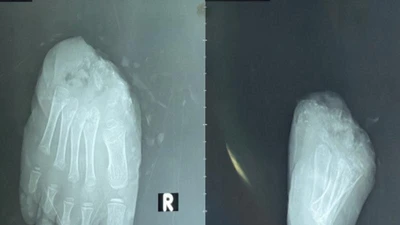

(PLO)- Trong quá trình điều trị COVID-19 cho bệnh nhân, đội ngũ y bác sĩ cũng đã phát hiện ông G.N bị tắc ruột và kết quả CT-Scan ghi nhận khối u ở đại tràng.